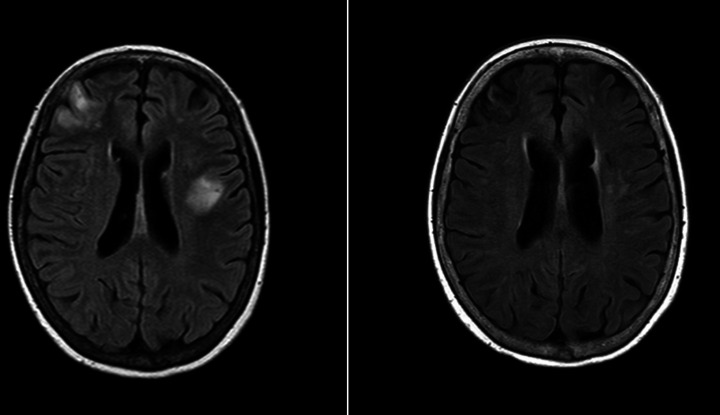

Here, we describe a case of a 71-year-old woman of Asian ethnicity who presented with an subacute neurological decline. The patient’s medical history was significant for bilateral deep vein thrombosis (DVT), type 2 diabetes mellitus, thyroid nodules and gastro-oesophageal reflux disease. Case 1 initially presented postbilateral below knee DVTs after a long-haul flight from the Philippines, which were managed with direct oral anticoagulants for 3 months. This was followed by presumed post-thrombotic syndrome, with violaceous cutaneous lesions on the upper thighs 1 year later. This was investigated with skin biopsy, with findings suspicious of IgG4-related disease, and blood tests finding polyclonal hypergammaglobulinaemia. The patient was subsequently managed with prednisolone and mycophenolate for presumed IgG4-related disease. The patient re-presented with two episodes of intracerebral haemorrhage 1 and 2 months post this presumptive diagnosis, with an initial MRI-brain demonstrated multifocal changes presumed to be related to cerebral amyloid angiopathy. The patient re-presented 1 month later with a subacute history of recurrent falls, progressive ataxia and dysarthria with associated constitutional symptoms over a 4-week period. An MRI brain on this admission demonstrated multifocal infarcts and focal cortical and subcortical haemorrhages (figure 1). At this time, she was noted to have anaemia, and thrombocytopaenia, with an elevated ferritin, negative fluorodeoxyglucose positron emission tomography (FDG-PET) scan, and bone marrow biopsy demonstrating mildly hypercellular marrow. The skin biopsy of the violaceous lesion on the thigh was repeated, with findings consistent with a diagnosis of intravascular B-cell lymphoma.

Figure 1.

MRI imaging for case 1, MRI brain (axial FLAIR) findings at onset of neurological illness with follow-up imaging over 1 year later demonstrating stable gliosis and encephalomalacia with no new lesions. FLAIR refers to fluid-attenuated inversion recovery MRI sequence.